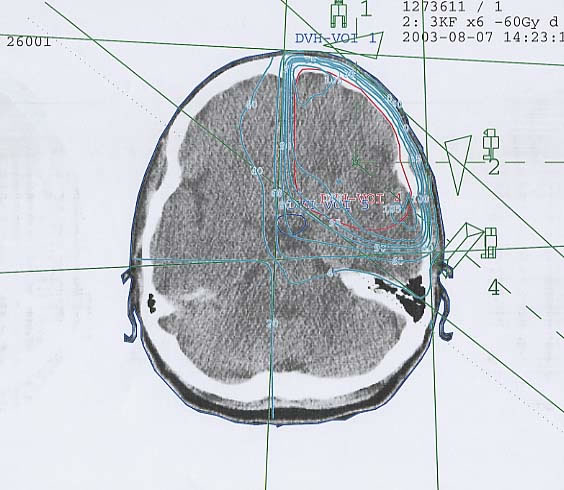

Hirntumore: Bestrahlungsplan

Bestrahlungspläne